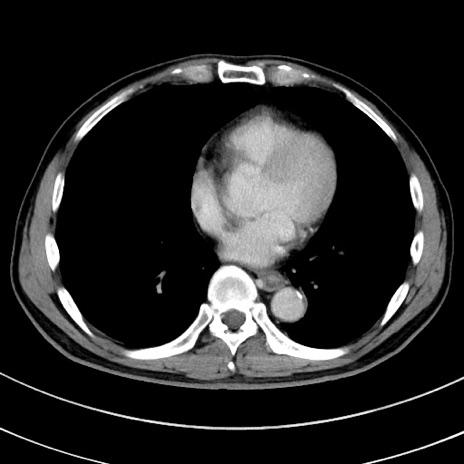

症例

冠状断像